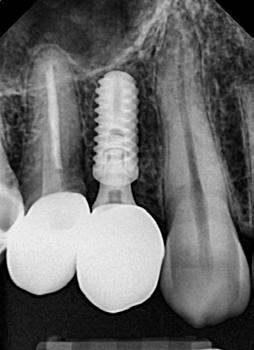

Az eljárást helyi érzéstelenítés mellett végeztük (4%-os articaine-hidroklorid 1:100 000 adrenalinnal). Papillakímélő, U alakú palatális bemetszést végeztünk, teljes vastagságú nyálkahártyalebeny preparálás történt, a lebenyt bukkálisan feltekertük (5. ábra). A lebeny bukkálisan feltekert részén de-epitelizációt végeztük el, amellyel kompenzálni tudtuk a bukkális lágyszöveti defektust. Szakaszos előfúrást végeztünk, és a bredent copaSKY 4x10 implantátumot 30 Ncm behajtási nyomatékkal helyeztük be (6. ábra). Az implantátumot 1 mm-re szubkresztálisan helyeztük be, hogy később szélesebb emergenciaprofilt tudjunk kialakítani (7. ábra). Az egyedi ínyformázó úgy készült, hogy kompozitot vittünk fel a titánbázisra, és így formáztuk a lágyszöveteket a transzgingivális gyógyulási fázis során (8. ábra). Az egyéni ínyformázó tulipán formájú, hogy kialakítsa a kívánt emergenciaprofilt. A lágyszövetet feszülésmentesen zártuk #6/0 nem felszívódó, monofil fonallal (Optilene, B. Braun Deutschland; 9. a–b. ábra). Posztoperatív röntgenfelvétel készült, ami alapján az implantátum a szomszédos fogakkal párhuzamos elhelyezést mutatott (10. ábra). Posztoperatív utasításokat adtunk a páciensnek a műtéti terület körüli szájhigiénia fenntartása érdekében. A beavatkozást követő egy héttel a varratokat eltávolítottuk, és a kezelt terület kielégítő gyógyulást mutatott (11. ábra). A 4 hónap utáni késleltetett terhelést a páciens kívánsága szerint terveztük.

értünk el (19. ábra). Az okkluzális nyílást tefloncsíkkal és kompozittal zártuk (20. ábra). Mindezek után, posztoperatív kontroll röntgenfelvétel készült, amely a pótlás megfelelő illeszkedését mutatta (21. ábra). A hat hónapos utánkövetés során jól megfigyelhető a teltebb lágyszöveti profil és a megtartott kresztális csontszint (22–24. ábra)

és 20. ábra: Kompozittal zárt okkluzális nyílás. 21. ábra: Röntgenfelvétel a végleges korona felhelyezése után.

22. ábra: A hat hónapos utánkövetés: kiváló emergenciaprofil. — 23. ábra: A hat hónapos utánkövetés: a lágyszövetek jelentősen megvastagodtak. — 24. ábra: Hat hónapos utánkövetési röntgenfelvétel; a kresztális csontállomány megtartott.